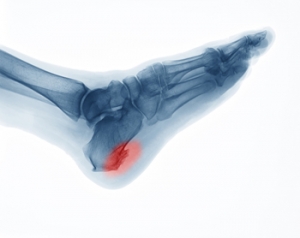

How Did I Get a Heel Spur?

A spur is a bony growth that may develop due to repetitive irritation or stress. As its name suggests, a heel spur develops on the heel bone or calcaneus. More specifically, it typically forms in one of two places on the heel bone. An inferior calcaneal spur forms underneath the heel bone and is associated with plantar fasciitis, a common ligament injury in the foot. A posterior calcaneal spur forms on the back of the heel bone and is associated with Achilles tendonitis. Heel spurs can be asymptomatic or cause sharp pain, dull aches, stiffness, and numbness in the affected heel. Corns and calluses also often form over the affected area. If you have painful heels, please see a podiatrist for a diagnosis and treatment.

Heel spurs are formed by calcium deposits on the back of the foot where the heel is. This can also be caused by small fragments of bone breaking off one section of the foot, attaching onto the back of the foot. Heel spurs can also be bone growth on the back of the foot and may grow in the direction of the arch of the foot.

Older individuals usually suffer from heel spurs and pain sometimes intensifies with age. One of the main condition's spurs are related to is plantar fasciitis.

The pain associated with spurs is often because of weight placed on the feet. When someone is walking, their entire weight is concentrated on the feet. Bone spurs then have the tendency to affect other bones and tissues around the foot. As the pain continues, the feet will become tender and sensitive over time.

How to Treat Heel Spurs

Heel spurs are calcium deposits that cause bone protrusions on the heel bone. Heel spurs are usually associated with plantar fasciitis, which occurs when the plantar fasciitis in the foot becomes inflamed. Typically, heel spurs don’t cause any symptoms. However, they can produce chronic or intermittent heel pain. Those who have had the condition often describe the irritation as a stabbing pain.

There are risk factors that may make you more likely to develop heel spurs. People who have abnormal walking gaits, run and jog on hard surfaces, are obese, or wear poorly fitting shoes are more likely to develop heel spurs.

Fortunately, there are precautions you can take to avoid developing heel spurs. One of the best ways to do this is by wearing well-fitting shoes with shock-absorbent soles. Another preventative technique is to choose running shoes if you plan on running, and walking shoes if you plan on walking. Shoes are made for different activities and it is important to research a shoe before you purchase a pair.

The pain associated with heel spurs often decreases the more you walk. However, a recurrence of pain after an extended period of rest or walking is likely to occur with this condition. Those with severe heel spur pain may opt to go the surgical route for treatment. However, more than 90% of those with the condition get better without surgical treatment. If you have a heel spur and want to know if surgery is right for you, you should go to your podiatrist and he or she will be able to conduct a pre-surgical test or exam to determine if you are an optimal candidate for surgery.